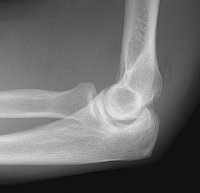

Case1: A 30 year old male fell while playing tennis.

Image 1: The lateral radiograph of the elbow demonstrates the presence of abnormal anterior and posterior fat pads, due to the presence of blood within the joint from a nondisplaced radial head fracture. CLICK TO ENLARGE.